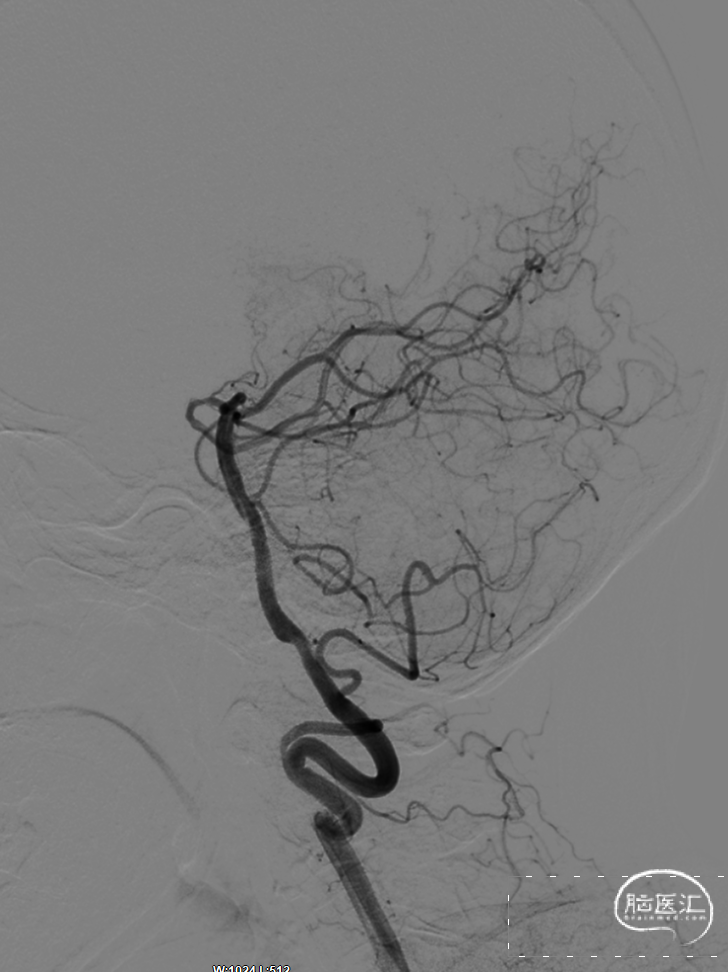

6

术后造影:

正位

侧位